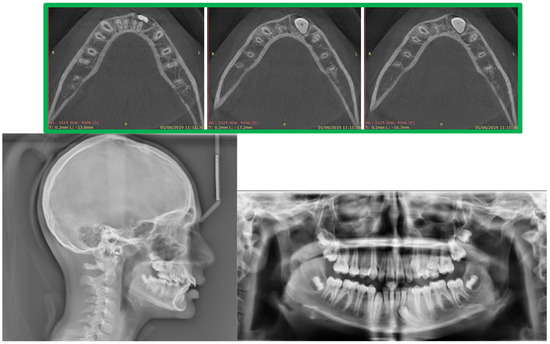

2.3. Treatment Progress

- Surgical exposure of the left mandibular canine using a diode laser (Doctor Smile, Lambda Spa, Brendola, Vi, Italy) for operculectomy and excision of fibromucous tissue. The corticotomy was performed using an ultrasonic piezosurgery system (Mectron Medical Technology, Carasco, Genova, Italy). A bottom (3M Unitek, Monrovia, CA, USA) was placed labially as close as possible to the canine’s coronal tip, combined with a metallic ligature and a cantilever (0.016 × 0.022 TMA, American Orthodontics, Sheboygan, WI, USA) without sutures (Figure 3a,b). The cantilever allowed for distal and buccal traction with light forces (1.7–2.8 ounces). A lingual arch was soldered (passive only on 31–32);

- Fixed multibrackets appliance (American Orthodontics Corp., Sheboygan, WI, USA, MBT prescription) were placed in the upper arch with 0.014 NiTi wire, bent back for controlling anchorage;

- After one month, a 0.016 NiTi wire was inserted in the upper arch;

- Fixed multibracket appliances were placed in the lower arch with a 0.014 NiTi wire, starting vertical traction of the canine. A bent back was used for controlling anchorage;

- After two months, the inferior left canine achieved a vertical position and reached its position in the arch. The bracket was replaced to adjust its axial inclination, and then a 0.016 NiTi wire was inserted;

- Before using stainless steel wire, a ligature from 16 to 26 and 36 to 46 for controlling anchorage was placed;

- 0.016 × 0.022 stainless steel wire was inserted in the upper and lower arches;

- 0.019 × 0.025 stainless steel wire was inserted in the upper and lower arches;

- Reverse Pin System” was placed on 13 and 23 to initiate class II biomechanics. Class II elastics (upper canines and first inferior molars) 3/8 4.5 ounces were used (Figure 3c). Class II elastics were used for 18 h every day;

- One year later, class I occlusion was achieved, and the class II elastics were used only during nighttime;

- Two years later, the appliance was deboned, and positioner retainers were given to the patient with the prescription to wear them every night.